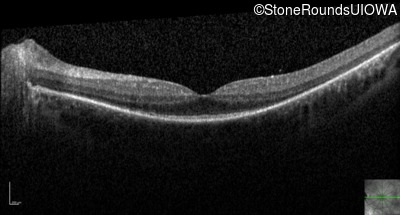

Optical Coherence Tomography - Right - 20/32 -1

Exemplar / OCT Stack

OCT Stack